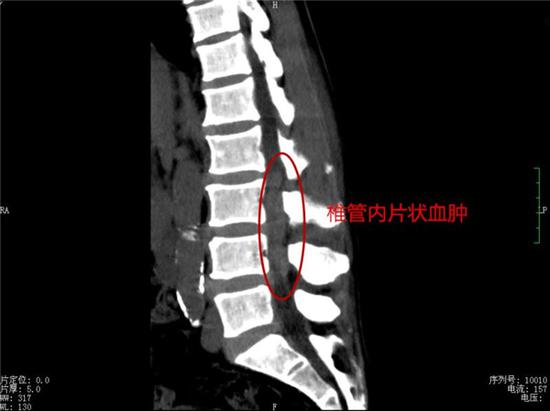

“ 目前,患者的腰、腿痛已经得到明显缓解,心、肺功能已逐步平稳,但是双下肢及大小便功能的恢复还需要一段漫长的时间。” 贺学军主任表示,自发性椎管内硬膜外血肿是比较少见的急症,国外报道其发生率约为 1/100 万,占硬脊膜外腔病变的 0.3%-0.9%。血肿可导致脊髓神经受压,出现肢体运动、感觉及大小便功能缺损症状,严重者导致患者出现截瘫,通常要求行急诊手术减压、清除血肿。

贺学军主任提醒,自发性的椎管内硬膜外血肿,没有明显的诱因,而且不同年龄阶段均可发生,病情隐匿,病程进展得相当快,数小时之内即有可能出现截瘫。如果患者出现不明原因的腰、腿疼痛、双下肢麻木、无法站立,切不可轻视,应尽早到正规专科进行诊治,切勿留下终身遗憾。